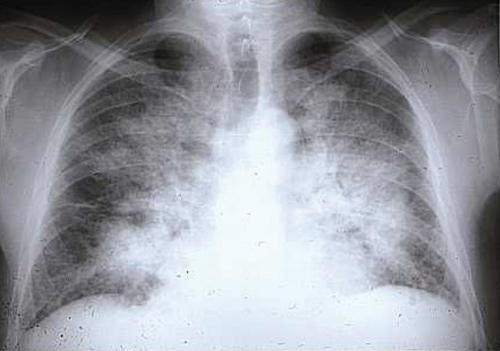

Seen in the chest x-ray, there are cardiomegaly and signs of pulmonary venous congestion with interstitial edema. Electrocardiagrams can also show disorders of ventricular repolarization, alterations in STEMI, left branch block, sinus tachycardia, disturbances of rhythm and other conditions of note.